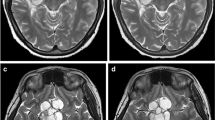

All imaging was performed on a single 1.5-Telsa MR scanner (Ingenia; Philips Healthcare; Best, the Netherlands) using the body coil transmit and a 15-channel receive only head coil. Clinical 2D T2-weighted (T2W) FLAIR (repetition time (TR)=11,000 ms, inversion time (TI)=2,800 ms, echo time (TE)=140 ms, acquired in plane resolution=0.79 mm×0.78 mm, 4-mm contiguous interleaved slices; compressed SENSE (CS) acceleration factor=1.6) images from our clinical imaging protocol were reconstructed with both standard CS (medium denoising) image reconstruction and AI “strong” denoising (selected from a 4-point scale provided by vendor: weak, medium, strong, and maximum) algorithm (SmartSpeed; Philips Healthcare, Best, The Netherlands). All T2W FLAIR images (Figs. 1, 2, and 3) were reviewed independently in a dedicated research picture archiving and communication system (PACS) by two study neuroradiologists, both with added qualifications in neuroradiology and one with additional added qualifications in pediatric radiology. The research PACS system used (Merge Healthcare, Version 8.1.6.7) allowed the radiologists to be blinded to patient information and clinical data during the review process; however, the radiologist was not blinded to image reconstruction method during side-by-side review. AI images were evaluated on a 3-point scale (poor, sufficient, excellent) for overall image quality, subjective assessment of signal to noise ratio (SNR), various artifacts, and diagnostic preference. Each sequence was also rated on a 3-point scale to indicate whether AI increased, decreased, or had no effect on image quality compared to the standard reconstruction. Additional imaging features were assessed and compared between the AI and standard reconstruction images and included CSF artifacts, motion artifacts, susceptibility artifacts, gray-white matter differentiation, image sharpness, flow void visualization, and extracranial structure evaluation (Supplementary Material 1). The presence of pathology, normal variants, or lack thereof were also commented on.

a-b Axial T2W FLAIR CS=1.6 brain MR images in an 8-year-old female presenting with repeated episodes of vomiting in the middle of the night without (a) and with (b) AI image reconstruction (SmartSpeed; Philips Healthcare). The AI image shows a reduction in image noise compared to the standard image reconstruction. There is also a focus of T2W FLAIR hyperintense signal in the right frontal white matter (arrows), doubtful clinical significance however is clearly reproduced on the AI reformat. Note is also made of a cavum septum pellucidum, normal anatomic variant, also accurately reproduced

a-b Axial T2W FLAIR CS=1.6 brain MR in a 8-year-old male with known diagnosis of tuberous sclerosis with standard (a) and AI (b) reconstruction demonstrating a dysplastic lesion in the right parietotemporal junction involving the subcortical and transmantle white matter (solid white arrows). There are additional smaller T2W FLAIR hyperintense foci in the bilateral periventricular white matter (dashed arrows), also accurately reproduced on AI reconstruction